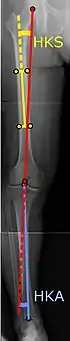

![]() |

Angles commonly measured before knee replacement surgery: |

To indicate knee replacement in case of osteoarthritis, its radiographic classification and severity of symptoms both should be substantial. Such radiography should consist of weightbearing X-rays of both knees: AP, lateral, and 30 degrees of flexion. AP and lateral views may not show joint space narrowing, but the 30-degree flexion view is most sensitive for narrowing. Full-length projections also are used in order to adjust the prosthesis to provide a neutral angle for the distal lower extremity. Two angles used for this purpose are:

- Hip-knee-shaft angle (HKS),[10] an angle formed between a line through the longitudinal axis of the femoral shaft and its mechanical axis, which is a line from the center of the femoral head to the intercondylar notch of the distal femur.[12]

- Hip-knee-ankle angle (HKA),[11] which is an angle between the femoral mechanical axis and the center of the ankle joint.[12] It is normally between 1.0° and 1.5° of varus in adults.[13]